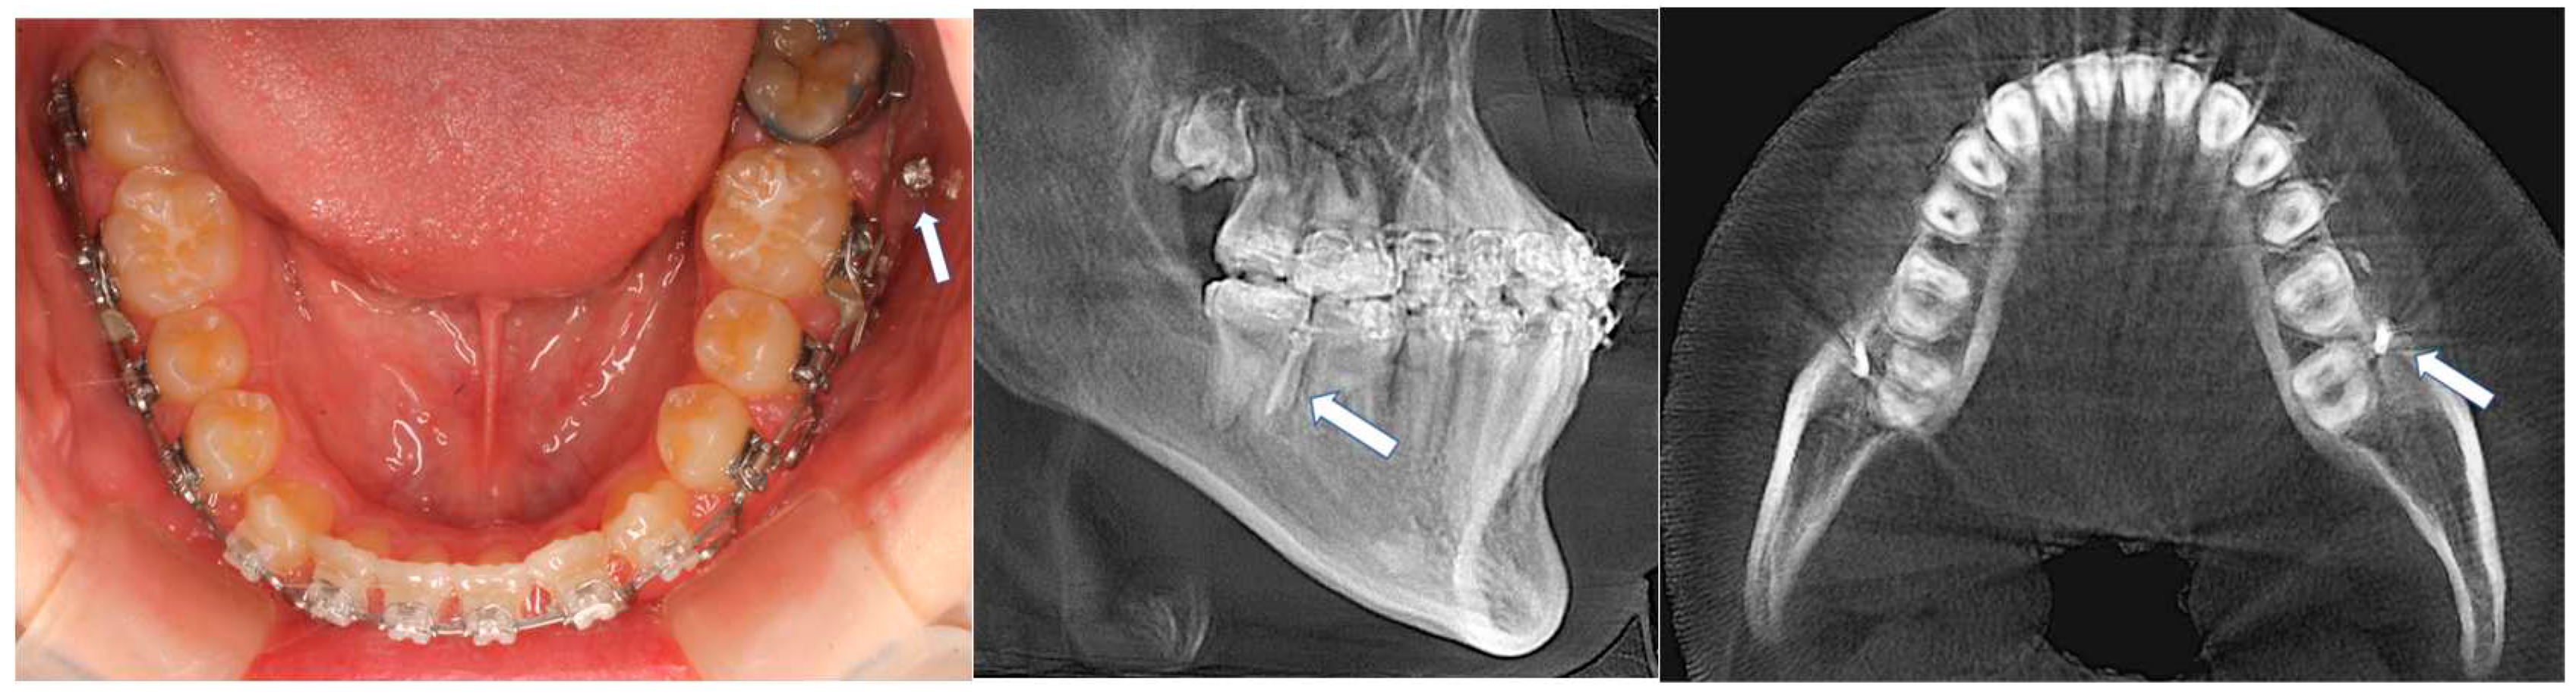

- In the mandible, TADs placement on the lingual side in the mandibular arch will be challenging, except there are torus lingualis that are large enough to provide TADs implantation; therefore, the buccal region is the only choice. The anterior part of the dental arch will have limited interdental bone availability, and the quality of bone is often questionable. A critical evaluation of available bone width is necessary before the implantation. Interdental space can be more suitable by appropriately placing the brackets to flare the crowded roots. Changing angulation of the roots beforehand is a common practice in placing TADs in the anterior region.